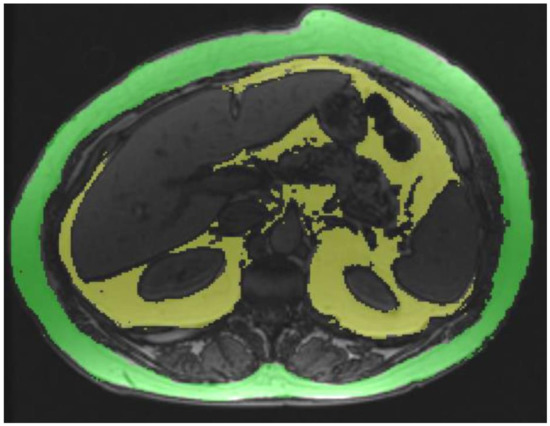

2.1. VAT and Subcutaneous Adipose Tissue (SAT) Estimation